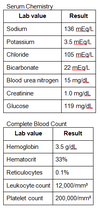

A 16-year-old African American man presents to the emergency department with sudden onset of weakness, shortness of breath, and fatigue. The patient denies chest pain and his mother explains that her son had symptoms of “the common cold” for the past few days. Further discussion reveals a family history of sickle cell disease. Examination shows the patient has scleral icterus and pallor. Cardiopulmonary examination is within normal limits and abdominal exam does not reveal hepatosplenomegaly. Chest X-ray is also normal. Laboratory results show:

Aplastic crisis

Aplastic crisis is characterized by severe anemia and reticulocytopenia(less than 1%). In patients with sickle cell disease, aplastic crisiscommonly occurs secondary to parvovirus B19 infection. Do not confuse aplastic crisis with aplastic anemia, which is characterized by pancytopenia.